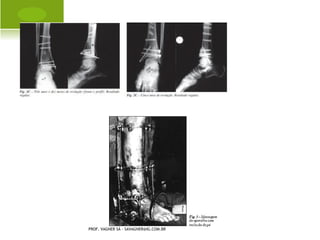

T RANSTROCANTÉRICA    E

SUBTROCANTÉRICA

DIÁFISE